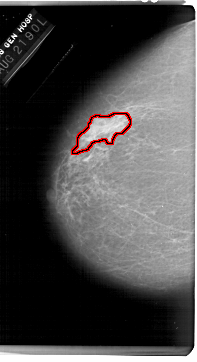

FILE: A_1215_1.LEFT_MLO.OVERLAY

TOTAL_ABNORMALITIES 1

ABNORMALITY 1

LESION_TYPE MASS SHAPE IRREGULAR MARGINS ILL_DEFINED

ASSESSMENT 4

SUBTLETY 4

PATHOLOGY MALIGNANT

TOTAL_OUTLINES 1

BOUNDARY